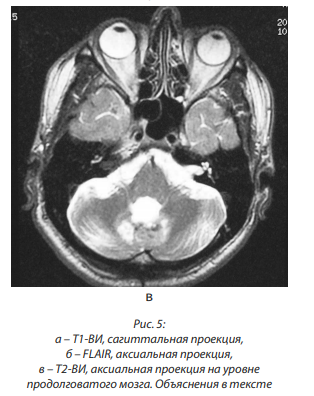

Выполнено СКТ головного мозга, СКТА, заключение: наиболее вероятно имеет место обызвествленное кровоизлияние в области каверномы червя мозжечка (рис. 1, а, б).

СКТА выявила вариант строения Виллизиева круга (круг разомкнут в области обеих задних соединительных артерий (ЗСА), левая ЗМА отходит от внутренней сонной артерии); наиболее вероятно имеет место обызвествленная кавернома червя мозжечка (рис. 3).

При МРТ головного мозга в сентябре 2016 г. выявлена умеренно выраженная компенсированная бивентрикулярная водянка; в проекции медиальных отделов правой гемисферы и червя мозжечка – зона постоперационных изменений размером 27×15×16 мм, со следами гемосидерина, правый выворот IV желудочка подтянут к зоне изменений, при контрастном усилении участков патологического накопления контрастного вещества не выявлено; атрофические изменения субкортикальных отделов обеих гемисфер мозжечка. Заключение: состояние после РТ ЗЧЯ справа, удаление каверномы червя мозжечка. Данных за рецидив не выявлено. Атрофические изменения субкортикальных отделов обеих гемисфер мозжечка (рис. 5, а, б, в).

МРТ головного мозга с контрастным усилением (2016 г.), заключение: состояние после ранее перенесенного оперативного вмешательства по поводу кавернозной ангиомы червя мозжечка с частичным ее удалением.

МР-картина множественных отложений гемосидерина в веществе мозга, что может быть характерно для амилоидной ангиопатии либо множественных мелких кавернозных ангиом головного мозга.

Атрофические изменения мозжечка.

При СКТА сосудов головного мозга (ксенетикс 300): состояние после удаления объемного патологического образования ЗЧЯ. В области оперативного вмешательства определяются множественные очаги и участки кальциноза. Максимальный размер участка обызвествления 10–11 мм, общий размер области участков кальциноза 28×28×17 мм. Плотность составляет от +88 до +445HU, Область участков кальциноза расположена по задней поверхности IV желудочка. После проведения ангиографии участков патологического накопления контрастного вещества не выявлено. Визуализированы мозговые артерии, просветы сосудов равномерные, кровоток симметричный, ЗСА контрастированы с обеих сторон.